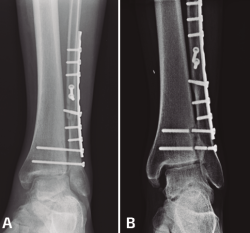

Figura 3. A: fractura suprasindesmal del peroné sintetizada con placa tercio de caña y 2 tornillos transindesmales; B: mismo caso a los 3 años de seguimiento con rotura de tornillos y apertura de la sindesmosis con cambios degenerativos tibioastragalinos.